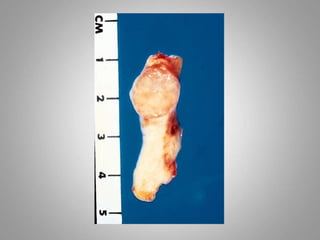

– Benign tumors :

• Remain localized

• Cannot invade

• Usually capsulated